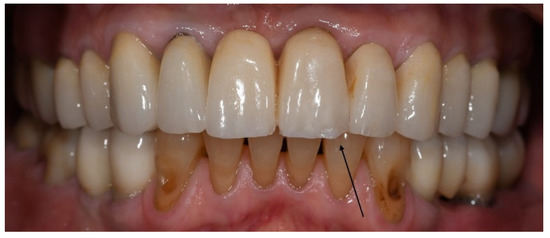

With regard to biological complications, the only complications that exhibited a borderline, although not significant, difference were three fractured teeth exclusively in the bruxer group (p = 0.051). The fractured teeth were in two different patients; one patient with two vital fractured premolars (first tooth after one year of function, the second after four years, Figure 1), and one patient with a non-vital fractured canine (after five years of function). Both patients did not wear an occlusal guard.

Figure 1. Patient with a fractured upper first pre-molar four years post-cementation. Three years prior, the same patient experienced fracture in an upper second pre-molar, which was replaced with a screw-retained implant restoration.